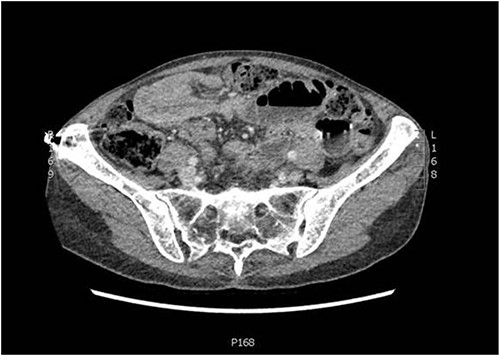

An independent 75-year-old woman presented to the emergency department with a 1-day history of crampy abdominal pain, nausea, vomiting and constipation. Her medical history includes multiple myeloma, which has been in remission for 4 years. She has no surgical history. On examination, she was alert but distressed with the pain. She was afebrile, normotensive and saturating well on room air with a regular pulse of 110, suggesting sinus tachycardia. Abdominal examination demonstrated a distended abdomen with tenderness around the umbilicus. There were no obvious hernias, and the rest of the abdominal exam was unremarkable. Her haematological investigations were unremarkable, and she had a lactate of 0.9 mmol/L. A computed tomography (CT) of her abdomen and pelvis with intravenous contrast was performed to investigate the cause of her pain. It demonstrated a partial or intermittent mid small bowel obstruction secondary to an intussusception (Figs 1 and 2).

Axial slice of CT abdomen and pelvis showing an intussusception.